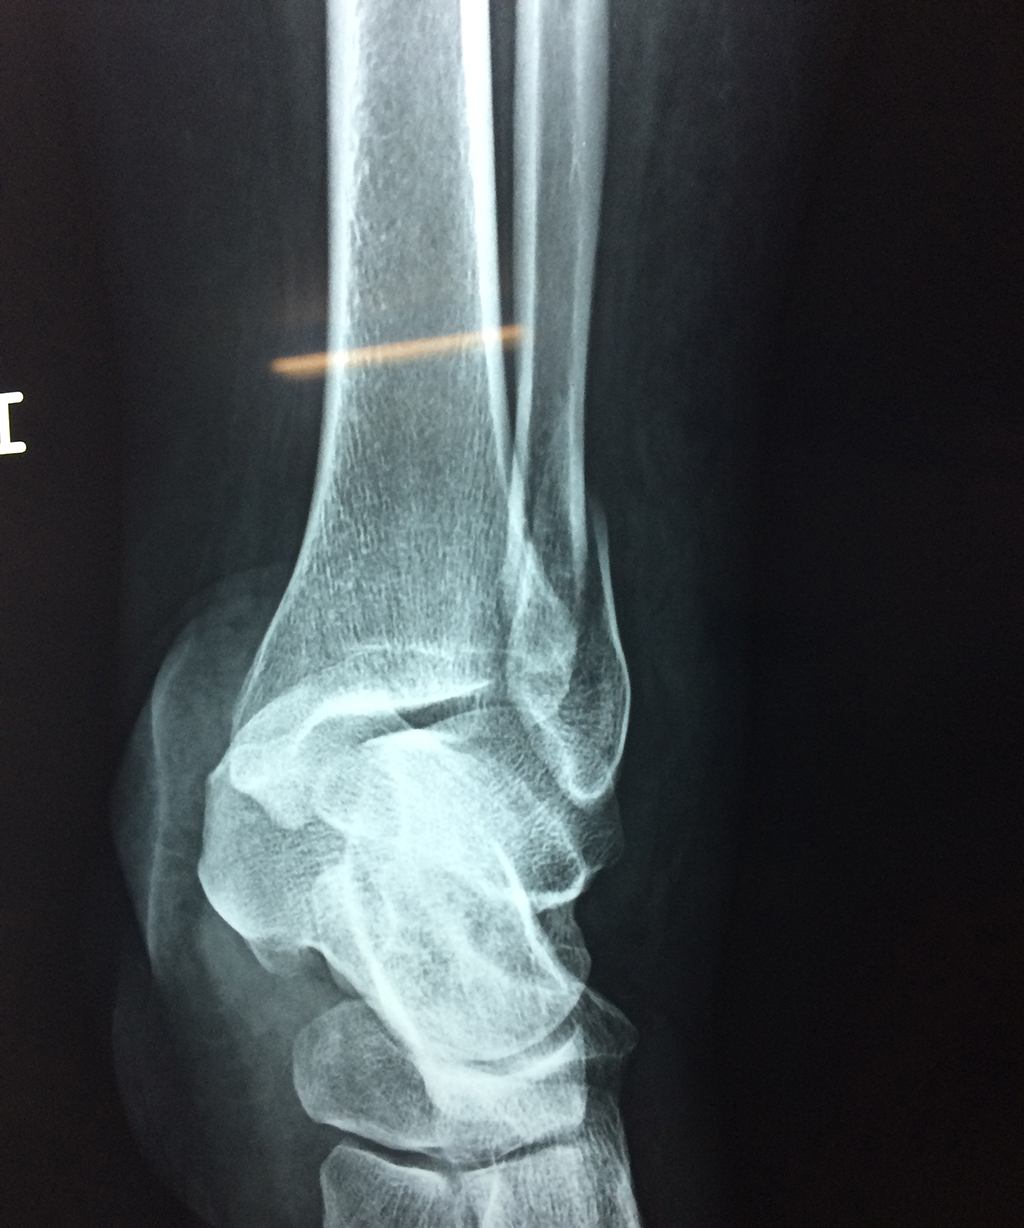

Una fractura de tobillo es la rotura de uno o más de los huesos del tobillo. Estas fracturas pueden ser:

- Los extremos de los huesos están desalineados entre sí (desplazados).

- La fractura se extiende hasta la articulación del tobillo (fractura intra-articular).

Cuando se necesita cirugía, es probable que esta implique el uso de clavijas de metal, tornillos o placas para sostener los huesos en su lugar mientras la fractura se consolida. Los elementos de soporte pueden ser temporales o permanentes.